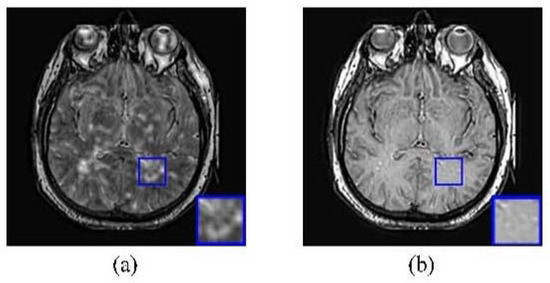

4.2.5. Extension of Proposed Solution